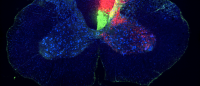

Now, a nerve stimulation therapy that Carmel is developing at Columbia is showing promise in animal studies and may eventually allow people with spinal cord injuries to regain function of their arms.

“The stimulation technique targets the nervous system connections spared by injury,” says Carmel, a neurologist at Columbia University and NewYork-Presbyterian, “enabling them to take over some of the lost function.” [read more]